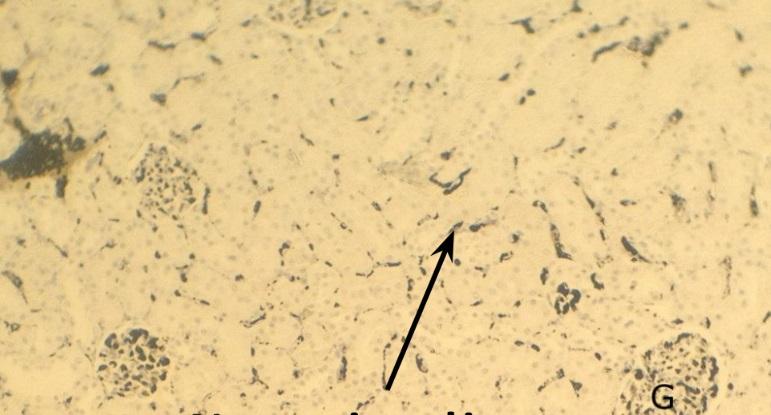

Pytanie 302

kłębuszek nerkowy (nerka, barwienie tuszem chińskim)